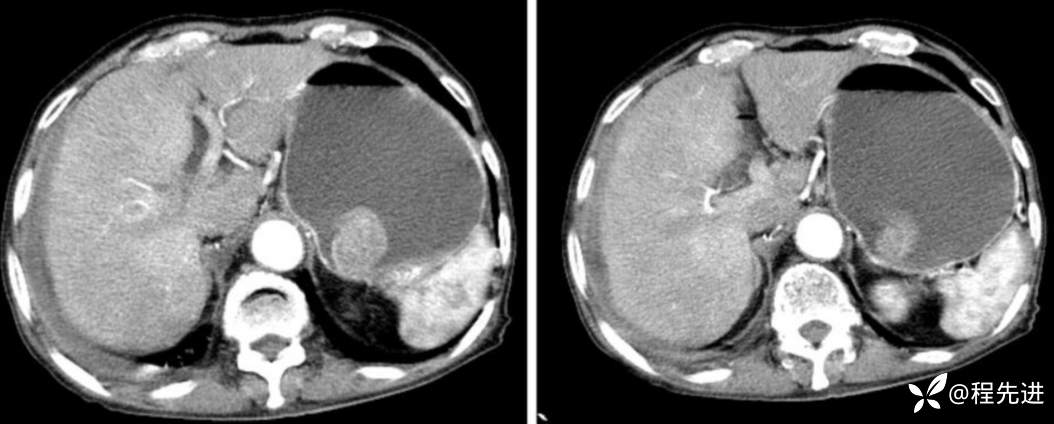

门脉期

延迟期